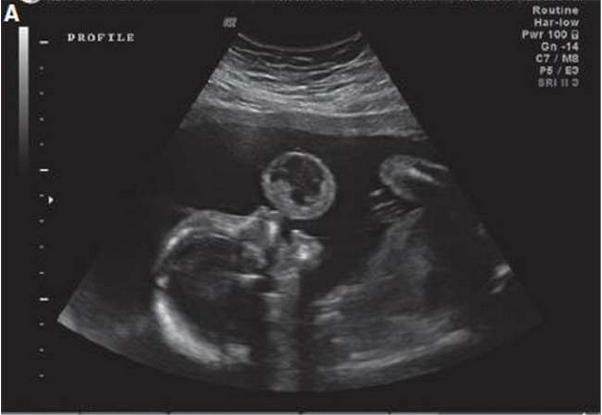

70个小时前产检孩子还是正常的,70个小时后孩子就没有了,这70个小时孩子到底经历了什么?

医生检查说10月1日,准妈妈来院检查时孩子胎心没了,羊水几乎没有了,羊水是保护孩子的屏障,羊水没了,子宫肌肉直接挤压孩子,孩子根本受不了的。